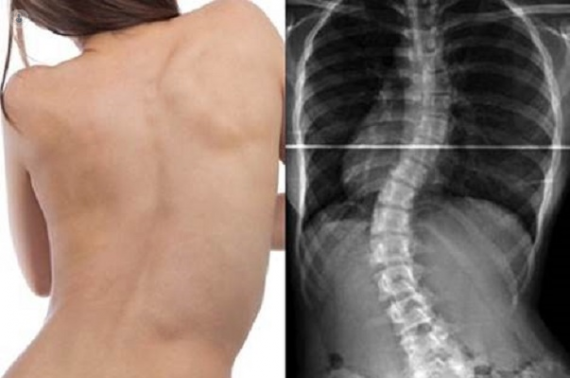

Si miramos una columna de perfil, la misma tiene curvas fisiológicas normales que permiten el buen funcionamiento del sistema muscular entre otras cosas, pero si la miramos desde atrás, debería ser recta.

Es la desviación lateral de una o más aéreas de la columna vertebral, la misma puede manifestarse en forma de "S" o de "C", comprometiendo a toda la columna directa o indirectamente.

Los pacientes con Escoliosis (dependiendo el grado), pueden presentar asimetría tanto en hombros como caderas (uno/a "más alto que otro"), por la desviación de la columna y el desequilibrio muscular. Una persona puede vivir toda su vida sin saber que tiene escoliosis, incluso no presentar síntomas, pero aquí se enumeran algunos de ellos: